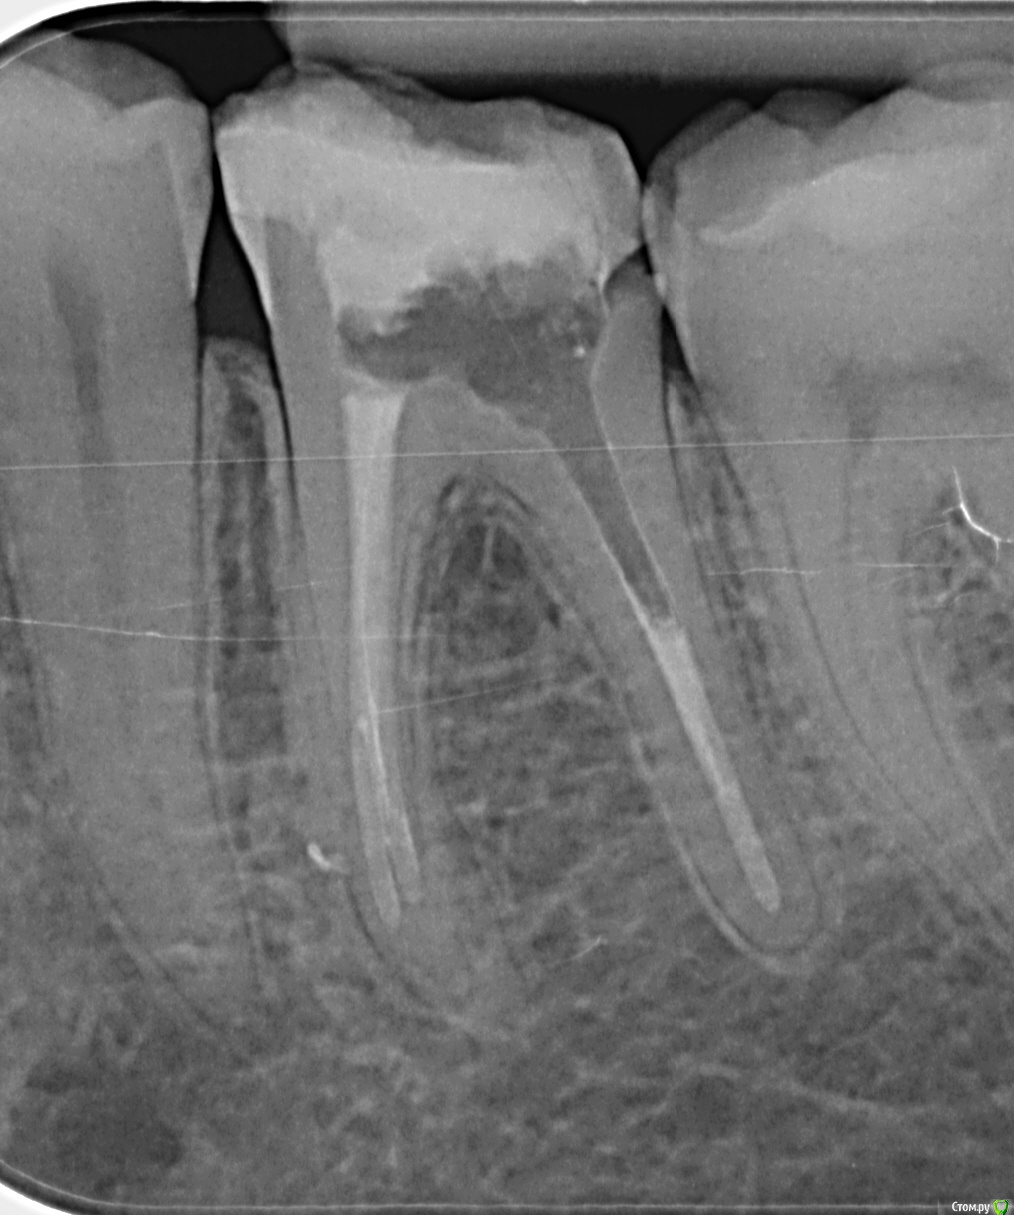

son-leta Опубликовано 19 апреля, 2017 Поделиться Опубликовано 19 апреля, 2017 Добрый вечер! Прошу рекомендаций по поводу лечения всех четырёх 6-к (если ещё что-то, то тоже). Зубы 1.6, 2.6 и 3.6 подготавливаются под покрытие коронками, нужно ли что-то перелечивать? И что делать с 4.6? Мы живём в Германии, врачи говорят разное. Ссылка на комментарий

son-leta Опубликовано 22 апреля, 2017 Автор Поделиться Опубликовано 22 апреля, 2017 По моему скромному мнению перелечивания не требуется, если с момента первичного лечения прошло не менее 2-х лет .Спасибо за ответ. 3.6 лечили 1,5 года назад, остальные зубы раньше Ссылка на комментарий